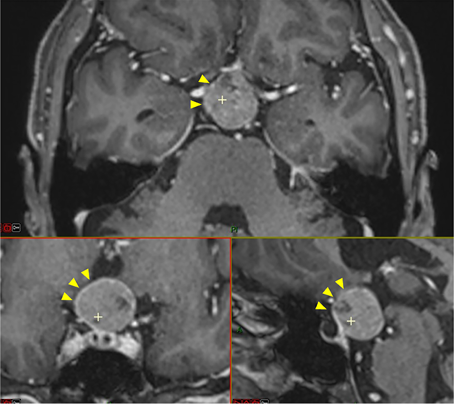

挑战环节一体现在肿瘤与垂体组织、视神经结构的粘连程度严重方面。磁共振影像显示,安娜的肿瘤呈现出球形特点,占据了垂体漏斗后部位置及鞍上间隙区域,与垂体柄区域和正常垂体组织呈现紧密相邻的解剖关系。

视交叉结构因为肿瘤的压迫作用已经出现明显的移位变形、组织变薄的状态改变,动眼神经同样受到一定程度的牵拉影响。肿瘤还与颈内动脉管壁、后交通动脉管壁、大脑前动脉管壁和大脑后动脉管壁呈现紧密粘连状态,术中进行剥离操作的难度极大,稍有不慎就可能引发大出血的紧急状况。